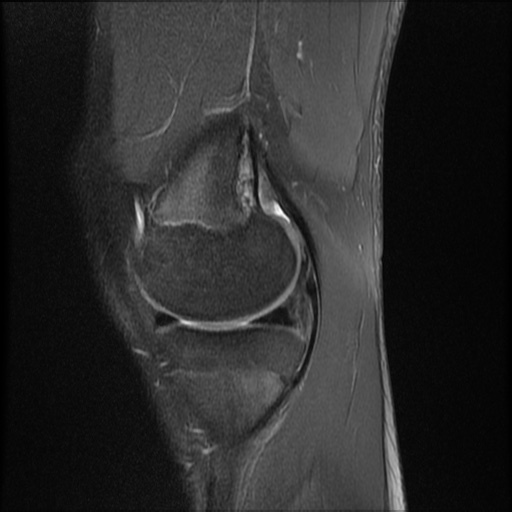

Fast Forward sign

Typical sign of a displaced meniscal tear aka the flipped meniscus sign.

A displaced tear of the lateral meniscus, in which the avulsed posterior horn is flipped towards the anterior compartment. This patient also had an ACL tear and a medial posterior horn meniscal injury.